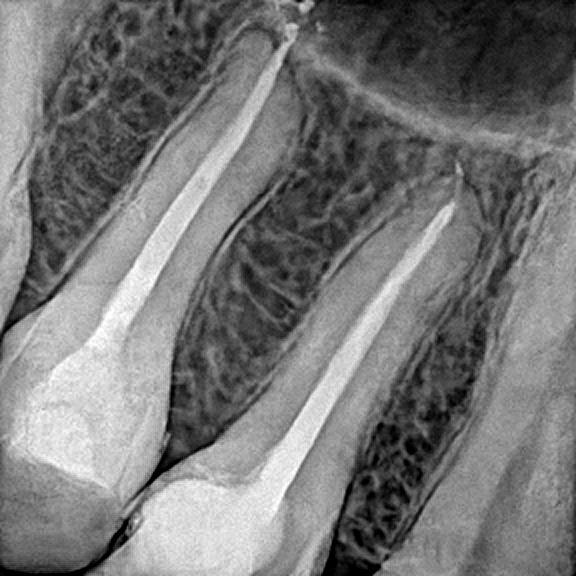

Uso do raio x digital, permitindo um melhor diagnóstico pro seu caso

Diagnóstico preciso para confirmar a necessidade do canal

Em alguns casos, a proservação (acompanhamento dos casos) é fundamental para sabermos se o tratamento está apresentando o resultado esperado e iremos solicitar que você retorne nos prazos estipulados (geralmente com 6 meses, 1 ano e 2 anos após o tratamento). Isso faz com que tenhamos certeza de que o seu dente está saudável